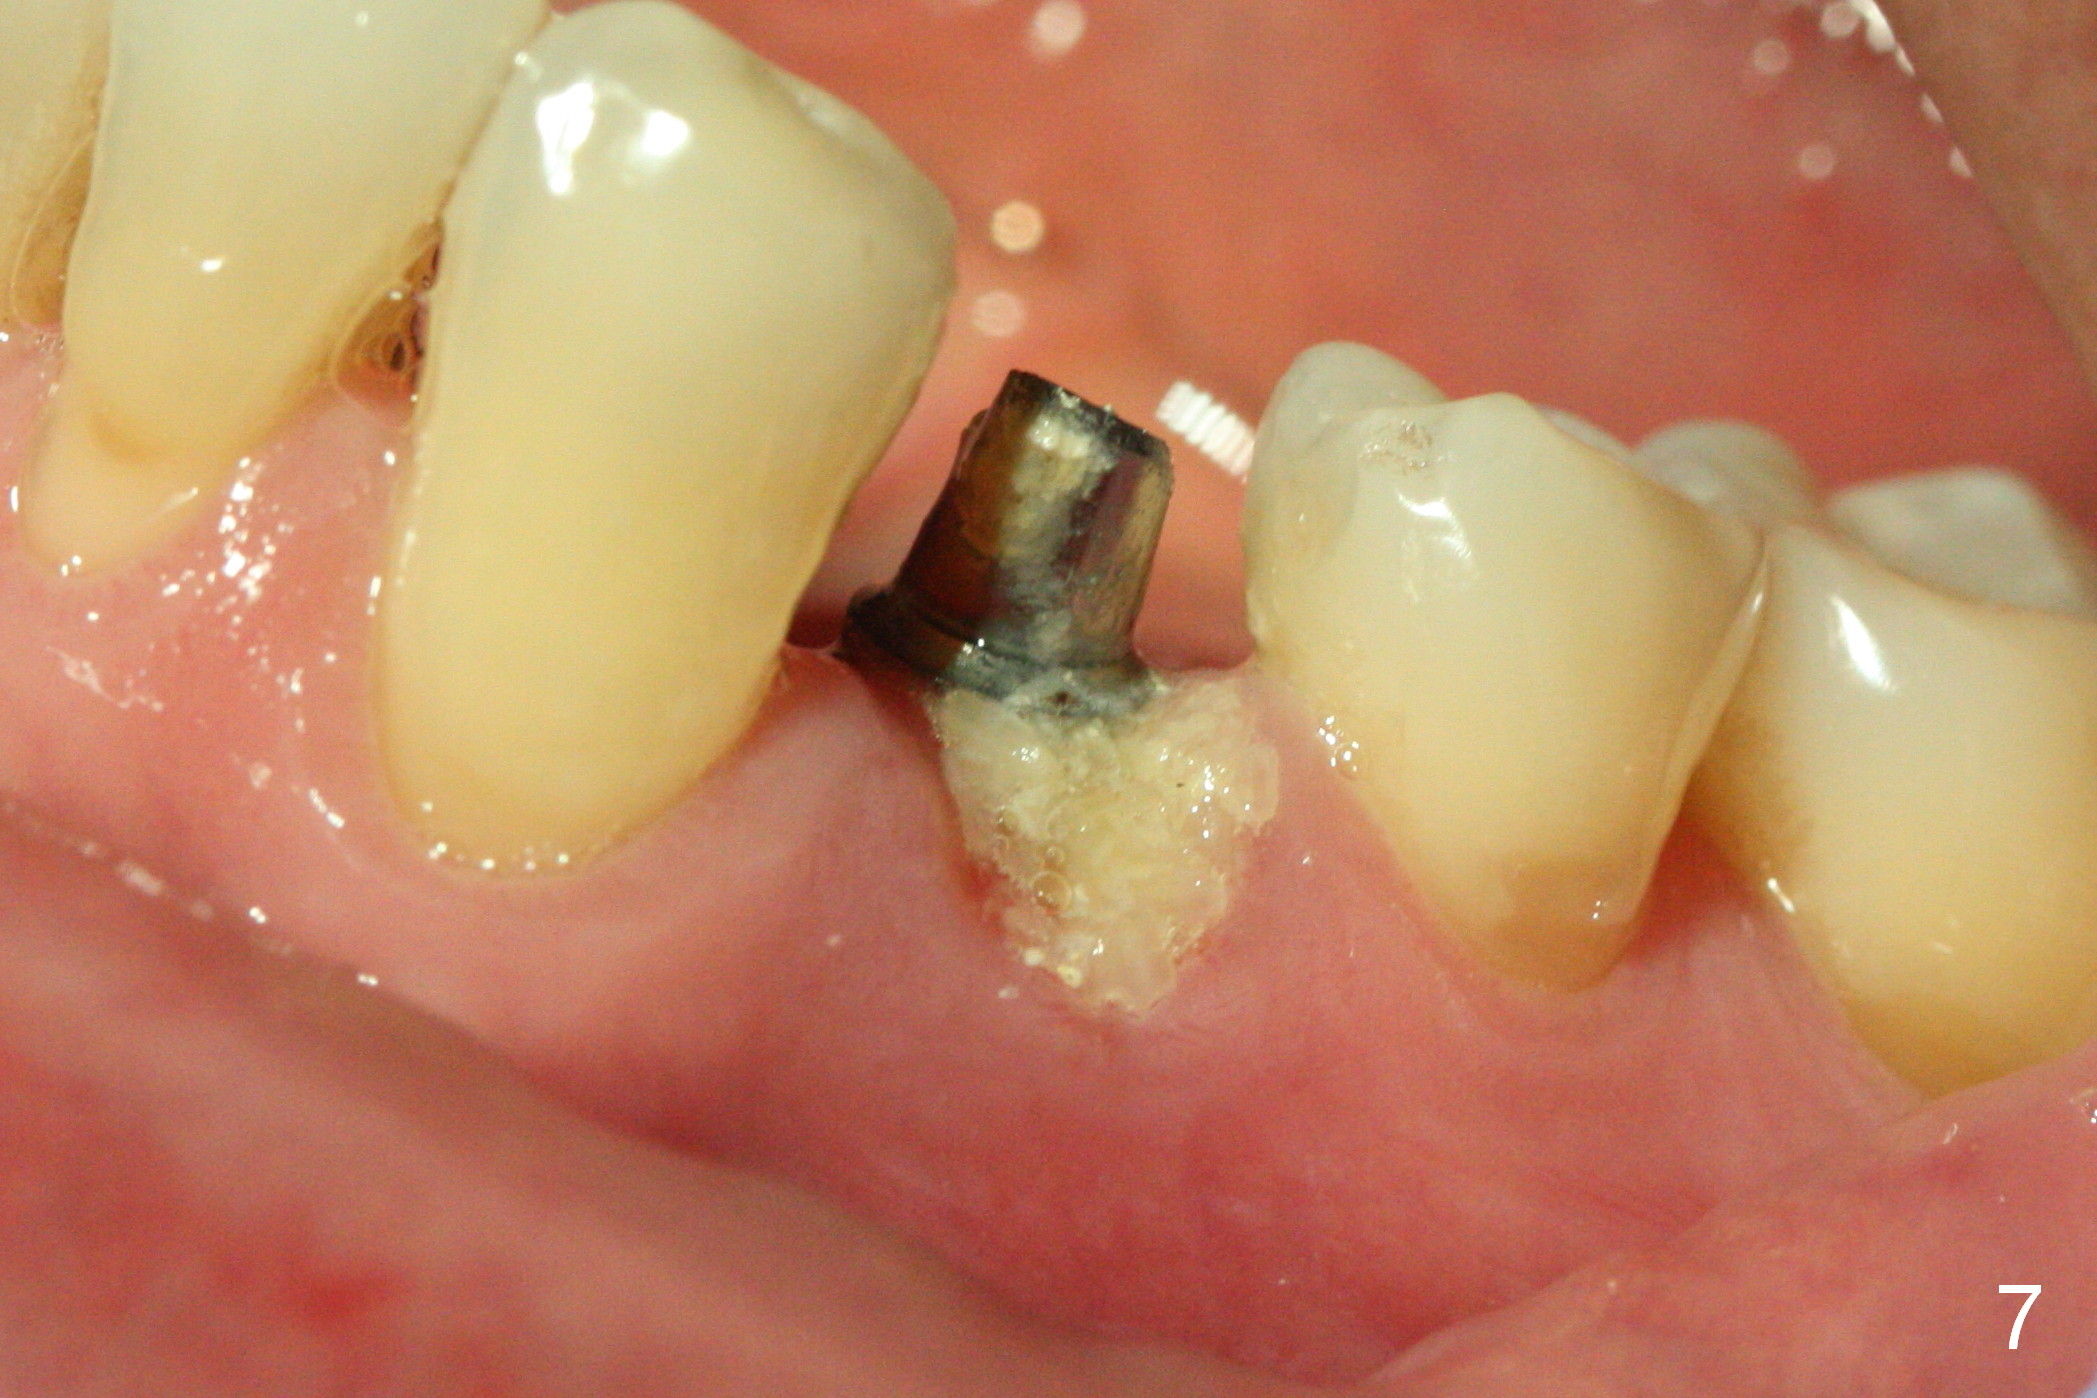

The patient returns for provisional revision 2 weeks postop (Fig.6).  The bone graft remains in place (Fig.7).  The buccal margin of the provisional is reduced (Fig.8).